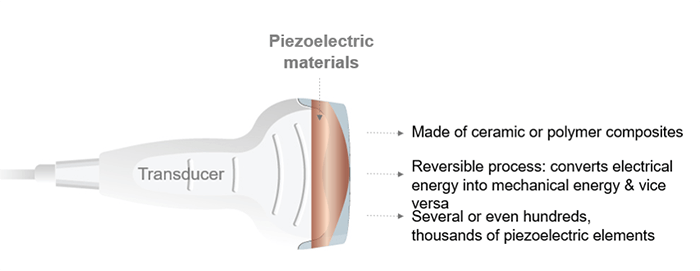

Piezoelectric materials are made of ceramic or polymer composites characterized by the reversible process, which converts the mechanical energy into electrical energy and vice versa. A transducer is composed of several or even hundreds or thousands of piezoelectric elements.

A common approach, any ultrasound transducer has the same role as an ear or mouth; it sends and receives ultrasound waves. The transducer is the hand part of the machine, responsible for the ultrasound production and detection. It converts the electrical energy into mechanical energy and vice versa, based on the piezoelectric effect.

As we mentioned previously, the ultrasound transducer is composed of one or more crystals called piezoelectric crystals. It might be composed of a single element or a band of multiple elements in rectangular or circular form. Besides, the element thickness is determined based on what resonance frequency is desired. Multi-element ultrasound transducers have the advantage that the ultrasound beam can be steered and focused electronically without moving the transducer by using electronic/digital delays in the activation of the different piezoelectric elements.